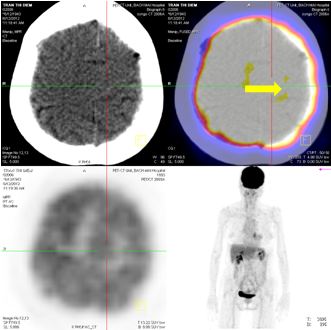

Chụp MRI sọ não: Sau xạ phẫu 6 tháng bằng dao gamma quay: khối u não tan biến hoàn toàn

Trước điều trị: u não 20×19mm

Sau điều trị 6 tháng: u tan hoàn toàn

Hình 6: Hình ảnh chụp MRI sọ não sau 6 tháng xạ phẫu bằng dao gamma quay: Khối u não di căn vùng đỉnh trái tan hoàn toàn

Trước điều trị: tổn thương thùy đỉnh trái 2 cm

Sau điều trị 6 tháng: tổn thương tan hoàn toàn

Hình 8: Hình ảnh PET/CT toàn thân sau 6 tháng điều trị: Khối u não vùng đỉnh trái tan hoàn toàn.

Hình 9: Hình ảnh chụp MRI sọ não sau 6 tháng xạ phẫu bằng dao gamma quay: Khối u não di căn vùng đỉnh trái tan hoàn toàn